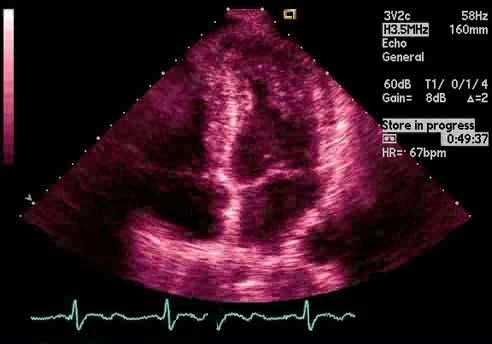

При гипертрофической кардиомиопатии (ГКМП), состояние стенки левого желудочка на УЗИ сердца является ненормальным в силу чрезмерного утолщения, при этом полость левого желудочка остается нормальной или будет небольших размеров. ГКМП часто присваивают термин «увеличенное сердце», но, вероятно, более точным было бы считать другое понятие «утолщение» или «мышечное» сердце. Распределение этой утолщенной мышцы (или гипертрофии) на УЗИ сердца могут принимать различные формы и сильно отличаются от пациента к пациенту (даже среди родственных больных).

В частности, стандартный, точный вид, или степень гипертрофии на эхокардиографии может значительно варьироваться среди пациентов, но степень проявления болезни может иметь значение у отдельных людей. Кроме того, абсолютная толщина стены может также существенно отличаться среди пациентов. ГКМП может достигать толщины, которое значительно превосходит таковую среди любых имеющих известность других сердечных заболеваний. Толщина стенки желудочка может возрасти до 6 раз выше нормы. Верхний предел нормальной толщине стенки 10-12мм и, что примечательно, некоторые пациенты могут показать толщину на УЗИ сердца не менее 40-60 мм. Пациенты очень часто сосредоточены на таком показателе при УЗИ сердца как точное измерение толщины стенки и «количество» массы левого желудочка. Но на самом деле у большинства пациентов это точное значение является малозначимый. Единственным исключением будут те пациенты, с чрезвычайно плотной стенкой толщиной более 30 или 35мм, для которых был доказан связанный повышенный риск внезапной смерти. С другой стороны, многие пациенты имеют только слегка увеличенную толщину, которая может быть ограничена только маленькой частью стенки левого желудочка, но вызывающей значительную обструкцию с для работы сердца.

Как правило, утолщения стенок на УЗИ сердца при гипертрофической описывается как асимметричная, который означает, что некоторые части стенки толще, чем другие. Обычно локализация гипертрофии основана на межжелудочковой перегородке, которая является увеличенной относительно свободной части стенки левого желудочка (т. е. не часть перегородки). Как правило, термин «концентрическая» означает только то, что все участки стенки такой же толщины; эта картина гипертрофии является редкостью при ГКМП, и присутствует только около 2% пациентов на УЗИ сердца.